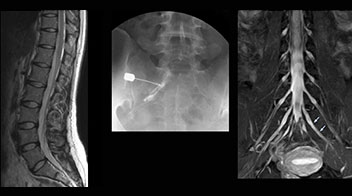

“In such case, we would then browse through axial T2-weighted MR images slice by slice and mentally reconstruct the actual situation based on both radiculography and MRI. Fortunately, NerveVIEW can now very well show nerve courses and presence of nerve compression or edema in one single image series.” “We have often seen NerveVIEW directly depict details of the nerve compression that were not observed by radiculography. Therefore, we think that with NerveVIEW we can reduce the number of invasive examinations, especially for some patients with lumbar plexus symptoms.”

“Before NerveVIEW, diagnosis by MRI alone was sometimes difficult, unless there was a strong suspicion based on clinical symptoms,” says Shoji Yabuki, MD, DMSc, Orthopedic surgeon at Fukushima Medical University School of Medicine. “This is why we routinely perform selective lumbosacral radiculography (nerve root block) and x-ray in such cases. However, radiculography can only depict nerves as far as the contrast agent reaches. When a nerve is distorted by compression, the contrast agent will not pass through this compressed area, preventing us from evaluating the full nerve compression.”

The key concept in MR neurography, Dr. Yabuki stresses, is the ability to directly visualize spinal nerves, versus inferring the presence of pathology indirectly. “Before NerveVIEW, we estimated compression of the nerve by looking for the presence or absence of fat signal on other MR images,” he says.